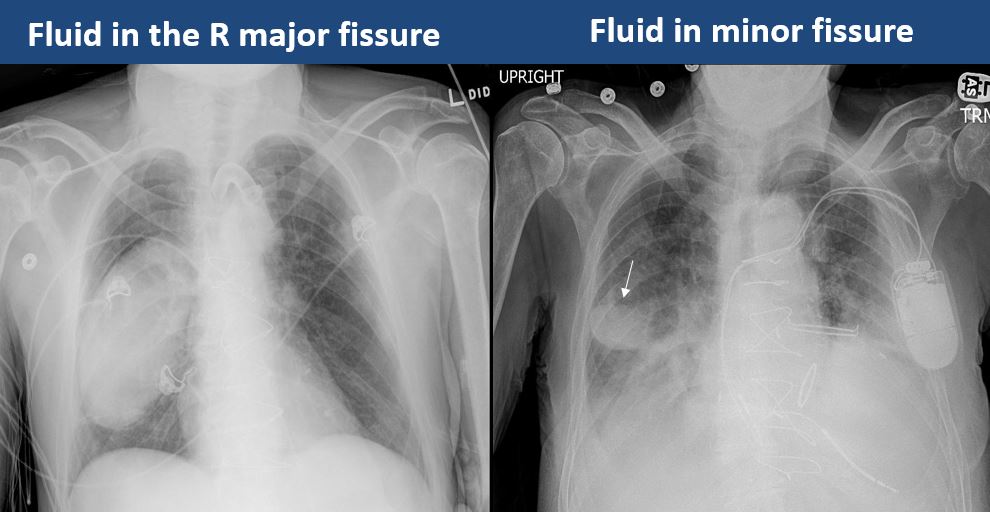

The position of the major and minor fissures is abnormal. [Yes/No]

There is focal fluid in the fissures. [Yes/No]